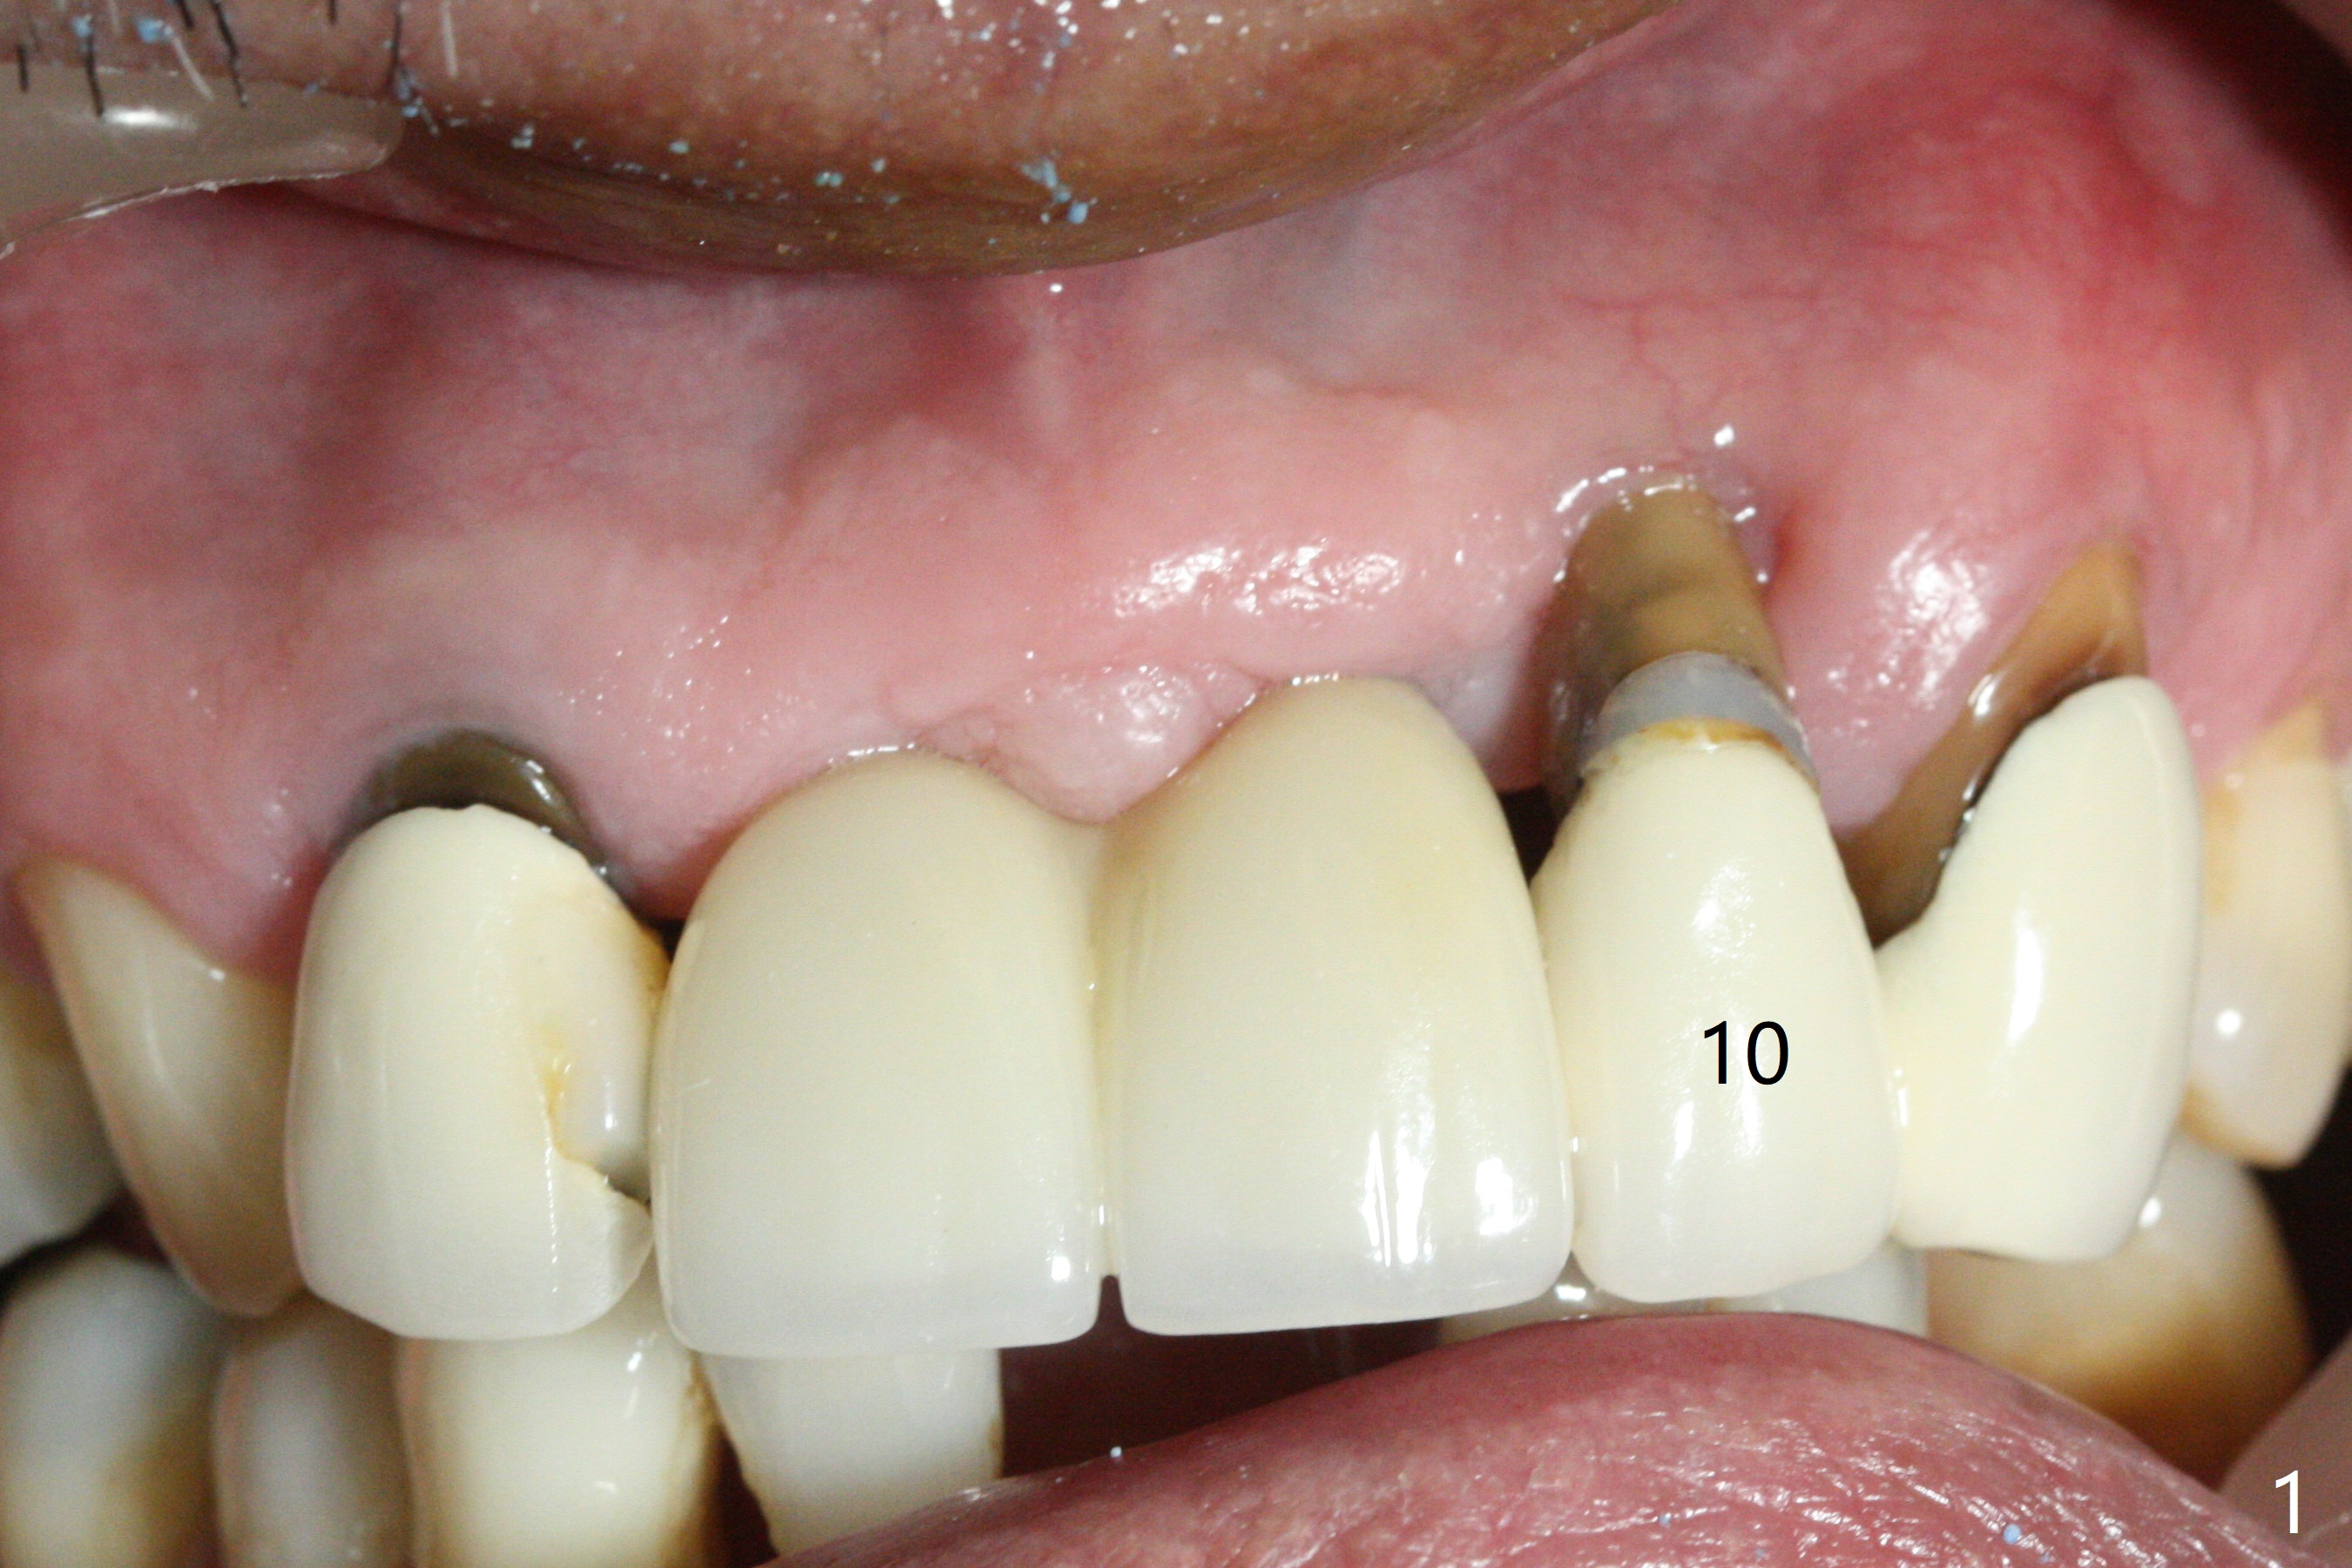

The tooth #10 has severe gingival recession (Fig.1) with loss of the buccal plate (Fig.2 *). After the initial osteotomy depth (Fig.3) increases by 2 mm, a 2.5x14(2) mm 1-piece implant is placed with insertion torque >60 Ncm (Fig.4). Palpation indicates the native bone apparently wider than CT shows. There is no sign of buccal or palatal plate perforation by palpation during osteotomy or implant placement. Vera Graft is placed repeatedly around the coronal threads (Fig.5-7 *). An immediate provisional is fabricated to close the socket (Fig.8). The buccal plate appears to collapse 1 month postop (cortical plate graft apparently more appropriate in this case); the margin of the provisional is trimmed so that the gingiva may grow incisally (Fig.9). The provisional dislodges several times postop due to short abutment. By nearly 4 months postop, the coronal bony defect seems to have been repaired (Fig.10 *). The tooth #11 has tenderness with bone loss (Fig.10 ^), corroborated by CT (distal bone loss, Fig.11 *). Since the apical bone is narrow (Fig.12), a narrow long implant is expected (Fig.13). Use an implant (3.5x13 mm) consistent with those at #14 and 15.